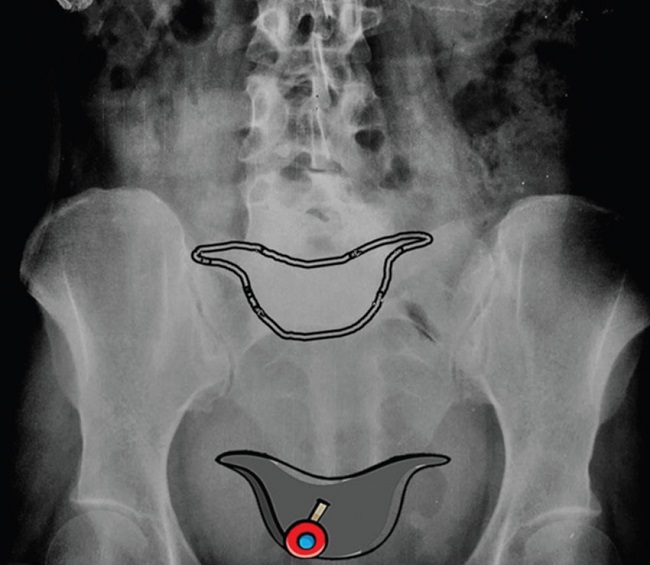

El signo del sombrero de Napoleón invertido se visualiza en las radiografías frontales de la columna vertebral lumbosacra. Representa una grave luxación del cuerpo de L5 sobre S1, sobrepasándolo y generando así la superposición de estructuras con la consecuente formación del sombrero1. Este signo radiológico fue descrito por primera vez en 1946, en un artículo publicado por Garland y Thomas, por su similitud con el conocido sombrero napoleónico2 (Figs. 1 y 2).

El “borde” o base del sombrero está formado por la rotación hacia abajo de los procesos transversales, y la “cúpula” del sombrero está formada por el cuerpo de L5, desplazado y caído, denominándose este proceso “espondilolistesis grave” o “espondiloptosis” (1.

La visualización del signo del sombrero invertido de Napoleón denota espondilolistesis grave o espondiloptosis de L5 sobre S1. Es importante reconocerlo, ya que se puede hallar incidentalmente en radiografías de frente de columna lumbosacra solicitadas por otro motivo, sin siquiera sospechar esta afección, y acompañarla de la incidencia de perfil para confirmar el desplazamiento del cuerpo vertebral.